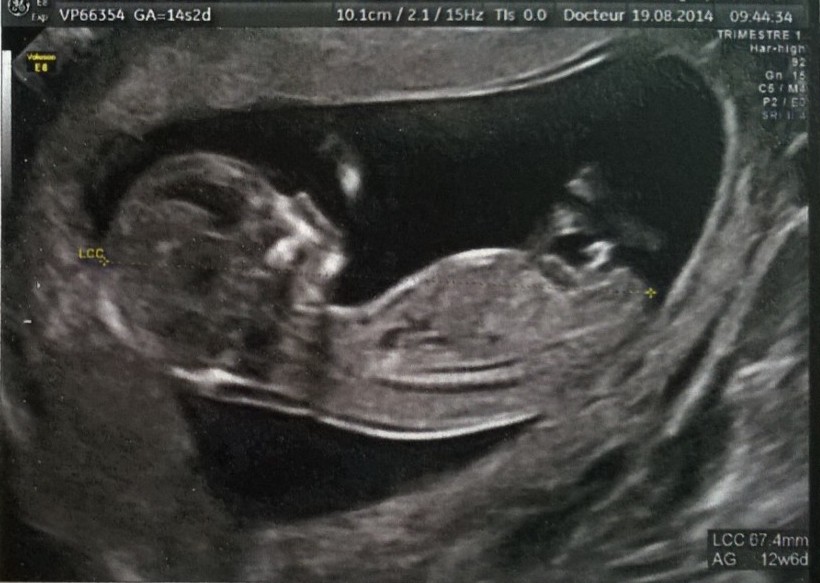

At my ob-gyn appointment this morning, the doctor looked at my 12-week ultrasound and said she could tell the gender from the angle of the genital tuber, which I'd never heard of. I asked of course, and she said she thought it was a boy.

When she explained it to me I could see it, but now after looking at other ultrasounds online I'm wondering if I was even looking at the right thing: I was looking at the reversed "J" shape, but isn't that just the umbilical cord? If it's the bud slightly to the right of that, isn't it still too bud-like to tell the angle?

Attachment 20612